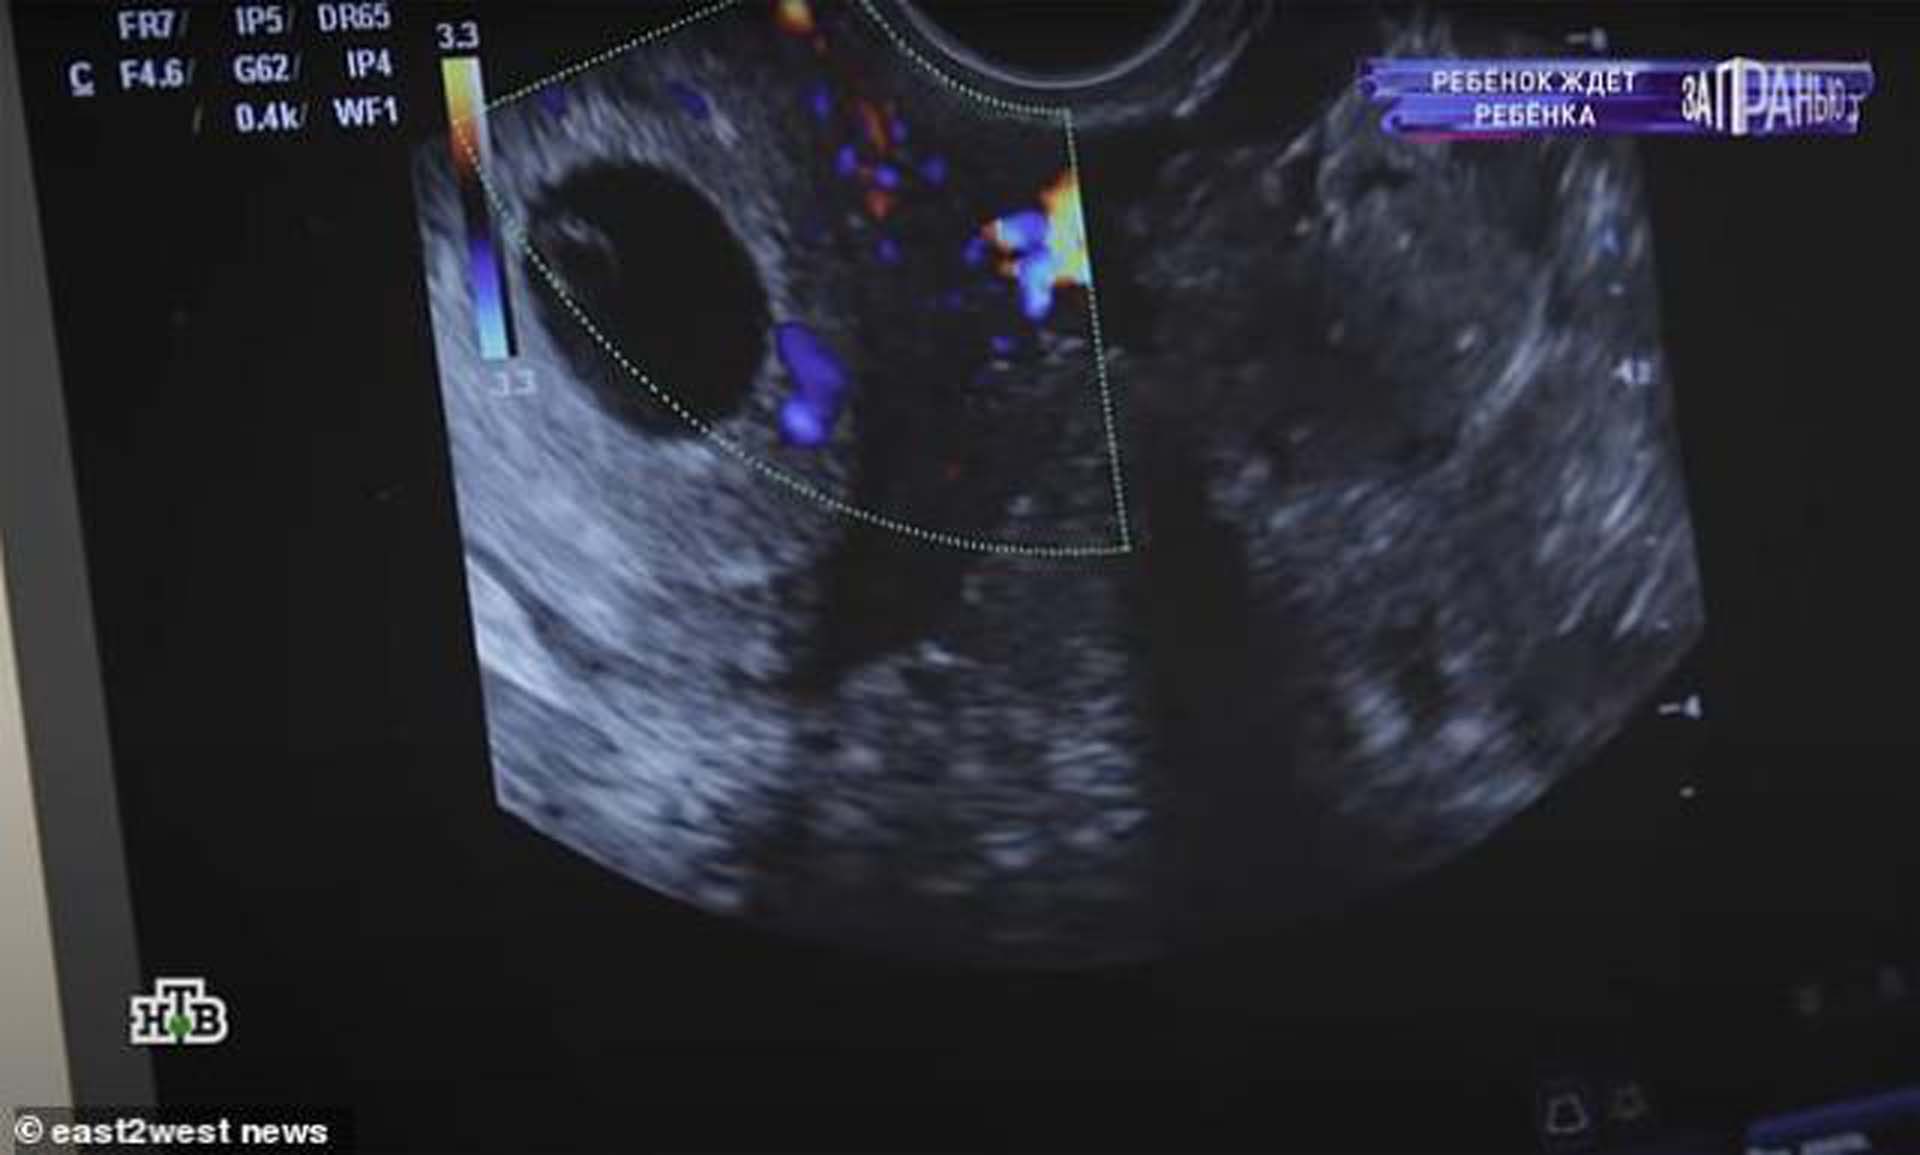

Dasha, birlikteliklerinin ardından hamile kalırken bu olay ülke gündeminde ilk sıralara oturdu. Rusya'daki özel bir televizyon kanalına konuk olan Dasha ve annesi, yaşanan durum karşısında çok şaşkın olduklarını ancak bebeğin dünyaya getirilmesi konusunda karar kıldıklarını ifade ettiler.